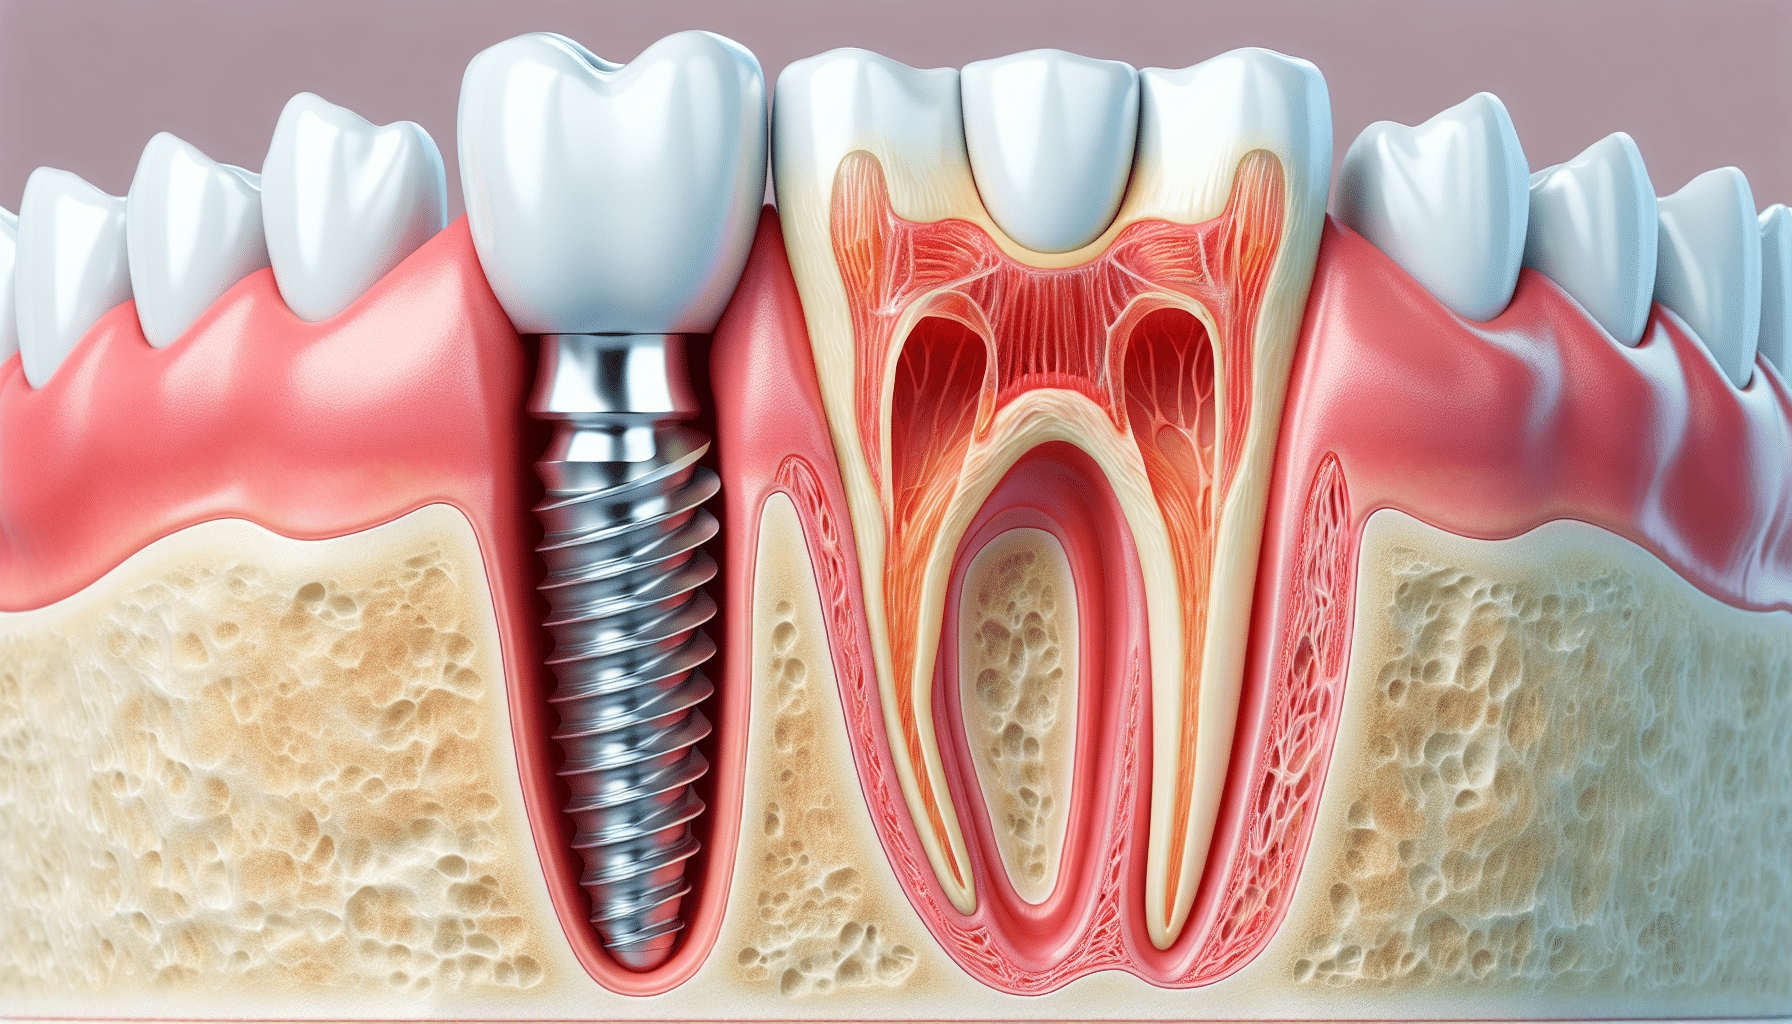

Understanding Dental Implants: A Comprehensive Guide

Dental implants have revolutionized the field of restorative dentistry, providing a durable and aesthetically pleasing solution for tooth loss. These titanium posts are surgically placed in the jawbone to serve as artificial roots for replacement teeth. In this article, we will explore various types of dental implants and related dental services, including single implants, immediate implants, implant-supported bridges, sinus lift procedures, and more.

Single Implants

A single implant is the ideal solution for replacing a single missing tooth. The procedure involves placing a titanium implant into the jawbone, allowing it to fuse with the bone in a process called osseointegration. Once healed, a custom-made crown is attached to the implant, restoring both function and aesthetics. Single implants are known for their durability and ability to preserve surrounding bone and teeth, making them a valuable dental services for patients in need of tooth replacement.